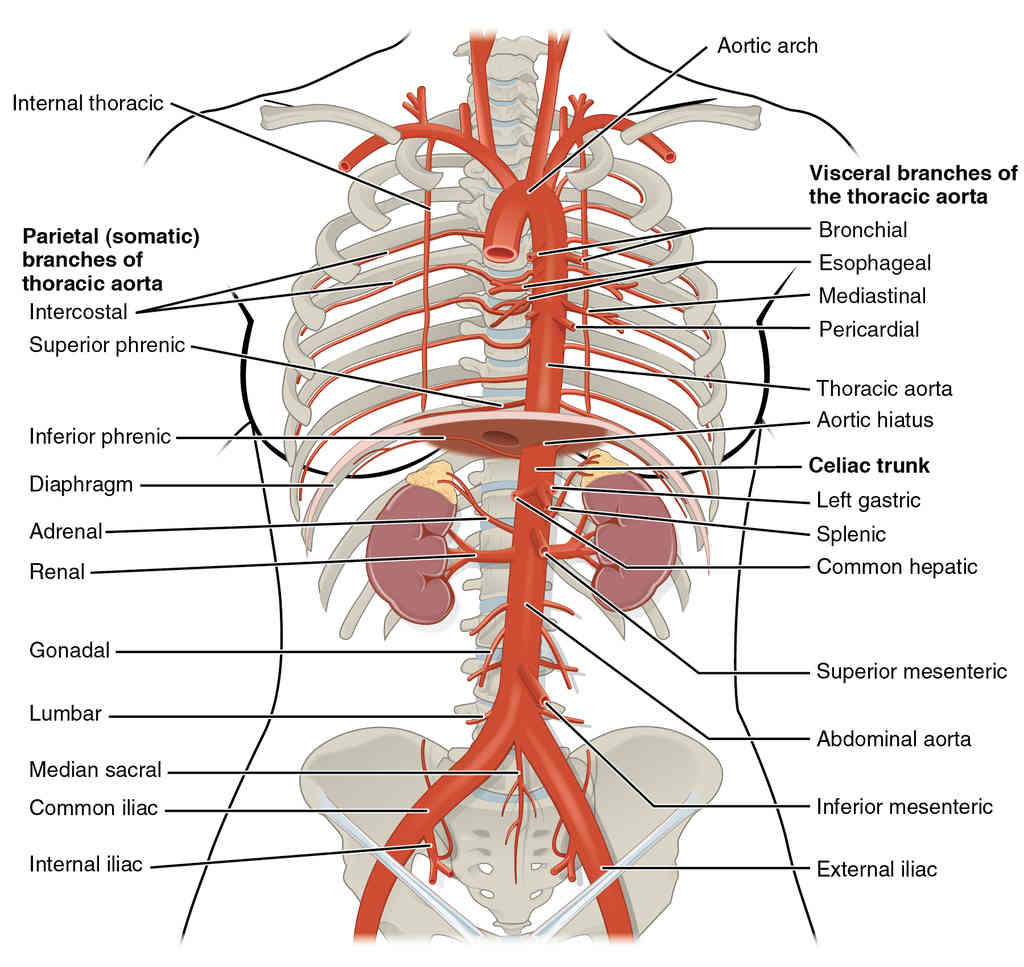

This page is under construction. For now, it is just a resource of the images found in the OpenStax Anatomy and Physiology Handbook. It wil slowly change into a revision tool. Each slide has a number. Use this to refer to the slide. When completed, it will have an unlabelled section, with labelled slides in parallel. On the unlabelled slides, write your answer and use the labelled slide to assess yourself. Keep track by also noting the number on each slide. Improvement at each attempt is important, more so than full marks on a first attempt.